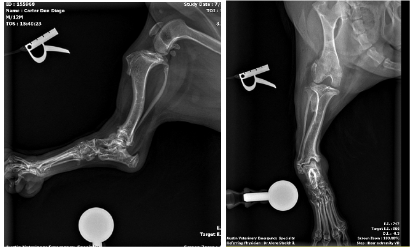

Sedated AP and lateral tibial radiographs (bilateral for surgical planning)

Pes Varus. This is a bone deformity attributed to eccentric medial closure of the distal tibial physis causing varus angulation or “bow-legging”. Most affected dogs are juvenile Dachshunds without a history of trauma, so a genetic cause is suspected. Most affected Dachshunds develop some degree of lameness. Treatment of Pes Varus is via surgical correction with a procedure known as a distal tibial corrective osteotomy. Surgical correction improves limb function, appearance of the limb and delays onset of osteoarthritis with the principal objective of correction being realignment of the joint surfaces proximal and distal to the deformity. Correction by open or closed wedge osteotomies stabilized with locking plates or an external fixator have been reported with excellent outcomes.